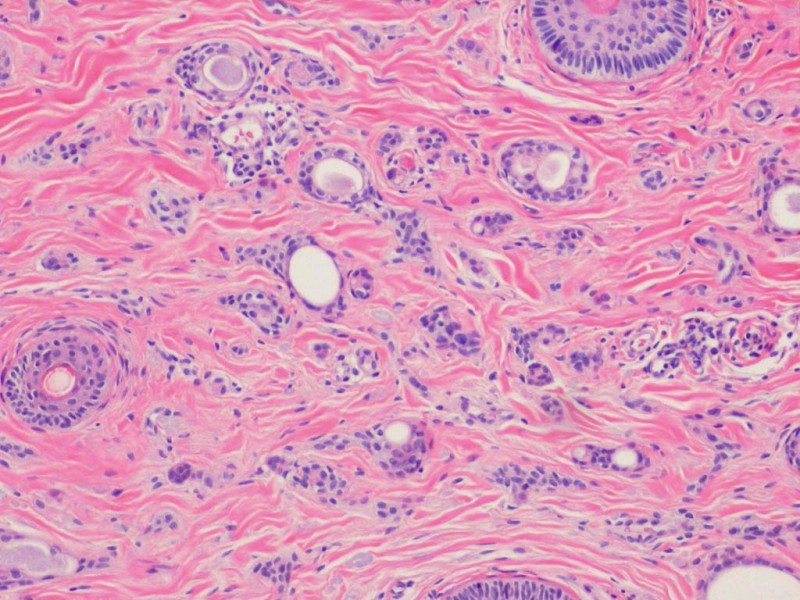

PA: Karakteristiek is het zien van kikkervisjes (tadpole),

een ronde structuur met een staartje eraan. Dit zijn schuin aangesneden buisstructuren.